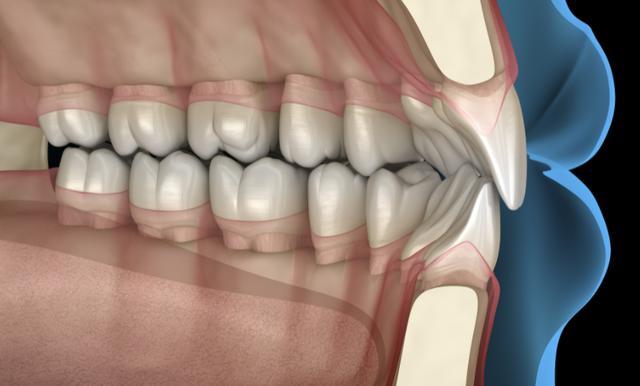

在日常使用中,种植体可能出现种植体松动、折断的情况,尤其是经常用种植牙咀嚼硬物,或者种植体安装时角度不当,会导致受力不均,进而引发牙槽骨吸收。

牙槽骨吸收后,会出现牙龈萎缩、种植体暴露的现象,不仅影响美观,还会进一步加重炎症风险。其中,老年人、骨质疏松患者的骨密度较低,骨吸收的风险更高。